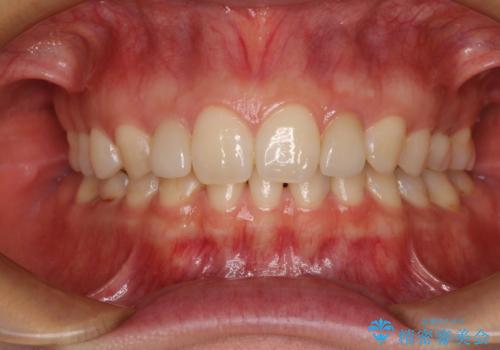

着色の原因として、湿気の多い環境で接着操作を行うと、境目に細かいギャップができてしまうことが考えられます。

接着の際にはラバーダムを使用して、乾燥した環境を整えて処置を行いました。